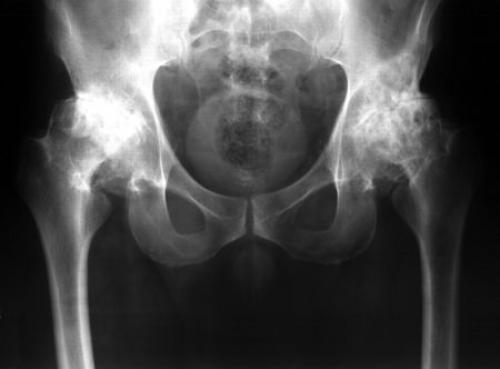

Виды переломов в области тазобедренного сустава. Нажмите на фото для увеличения

Прогноз: при своевременном обращении легкие и средней тяжести повреждения излечиваются полностью – в 90 % случаев, тяжелые со временем становятся причиной артроза и других осложнений – в 70 % случаев.